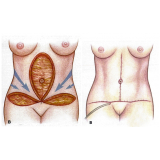

Abdominoplastia com Lipo

Há momentos em que é necessário ter por perto profissionais qualificados e dedicados à pronta recuperação do paciente. A FF Cirurgia Plástica oferece e coloca à sua disposição o que existe de mais atualizado em procedimento cirúrgico para abdominoplastia com lipo. Com o objetivo de levar qualidade à vida dos clientes, a instituição oferece infraestrutura adequada às necessidades de cada um: cuidado médico humanizado, realizado através de dedicação, profissionalismo e amor.